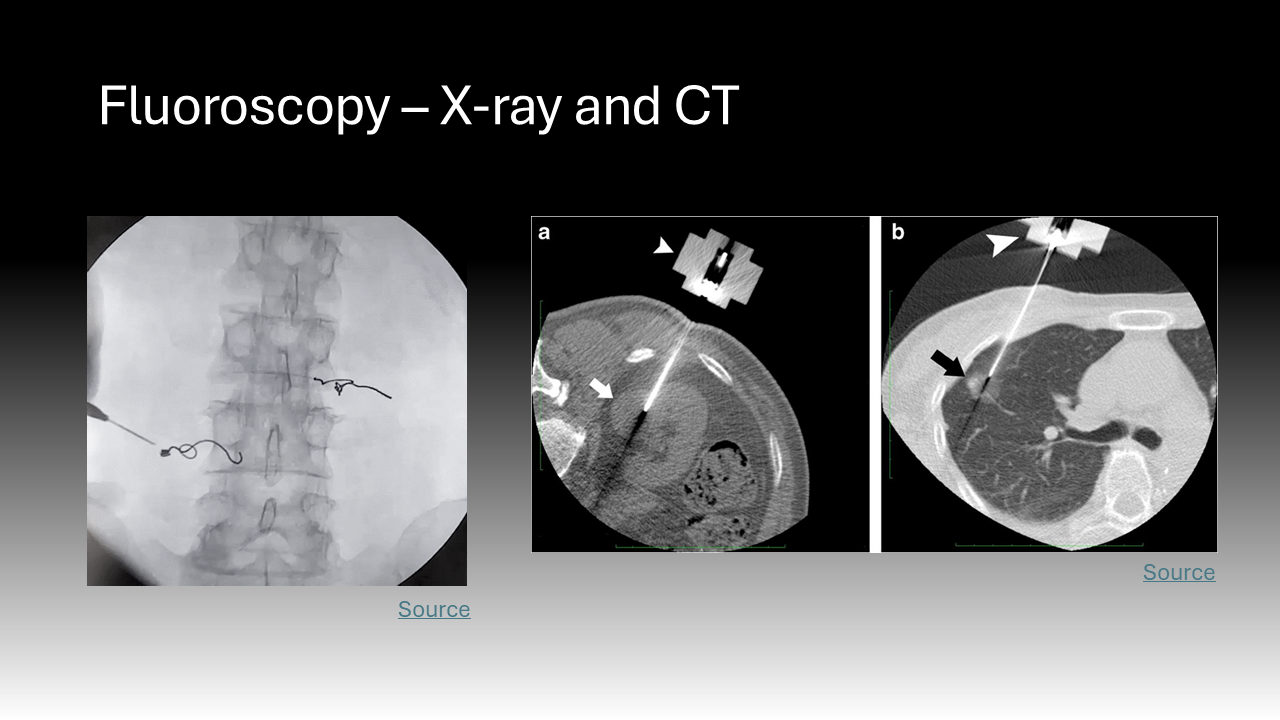

Ionizing radiation encompasses all high-energy rays that detach electrons from atoms. The body absorbs a fraction of this energy, which is disruptive at the molecular level.2 Ionizing radiation is found at low levels in the natural environment but has been employed at higher doses in medicine since the late 19th century.3 X-rays are ubiquitous in healthcare; this ionizing radiation has been the basis of two-dimensional diagnostic images and CT scans for years but is now employed during procedures.3 Cardiologists, neurosurgeons, orthopedic and vascular surgeons, and interventional radiologists all use live, continuous fluoroscopic imaging intraoperatively for “real-time feedback” during procedures.4 This technology not only allows for more accurate interventions but enables the use of minimally invasive approaches that replace open surgeries.4 In sum, the expanding use of X-ray technology in medicine, especially over the past 20 years, has led to more efficient diagnosis and treatment that is safer and more tolerable for patients.5 However, it also exposes a more diverse number of physicians to radiation and its harmful effects.5 Whereas X-rays during a diagnostic image or cancer radiation treatment are delivered to a physically isolated patient, physicians must be in close proximity to patients and radiation sources to perform procedures.5 This creates the current dilemma where healthcare providers now comprise the largest group of workers exposed to radiation in the world.5

The effects of radiation are dose-dependent.6 This means that while the potential damage from the low doses of radiation used during a medical procedure is slight, it is the cumulative effects of this chronic exposure in healthcare workers that are worrisome.6 It is logistically challenging to track radiation exposure in the healthcare setting because there are different types of dosimeters and various sets of guidelines for their use that differ by institution.7 Additionally, though they are mandated to wear dosimeters, individuals vary in their compliance with safety practices and protective shield use, which will be discussed later.7 While data on US physicians is lacking, several retrospective cohort studies in Europe have determined levels and trends of radiation exposure in healthcare workers.7 The standard unit for radiation is a gray (1 joule of energy absorbed by 1 kilogram) but when considering the harmful effects of radiation, grays are multiplied by a quality factor to convert to Sieverts (Sv).4

The use of fluoroscopy mainly exposes surgeons to scatter radiation, which is a lower dose as opposed to direct radiation that patients experience.8 However, this scatter radiation exposure in physicians accumulates significantly over time. Prior investigation demonstrates that spine surgeons using fluoroscopy are exposed to an average of 1.06 uSv per screw.8 Spine surgeons may place as many 30+ screws per day, 3-4 days per week, multiplied over a 40-year career.8 To put this in perspective, studies of survivors of the Hiroshima bombing have shown that being exposed to just one Sv is associated with a 60% increased chance of developing a solid malignancy.8 While the use of fluoroscopy is critical for patient safety and surgical success, the exposure experienced by physicians accumulates significantly over time.8